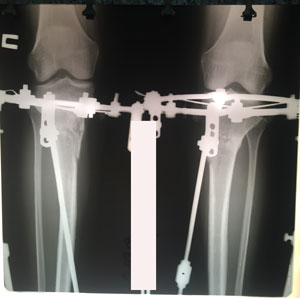

Исходник - 25 лет.

Дата операции - 11.07.2019г.

в процессе работы

на фиксации